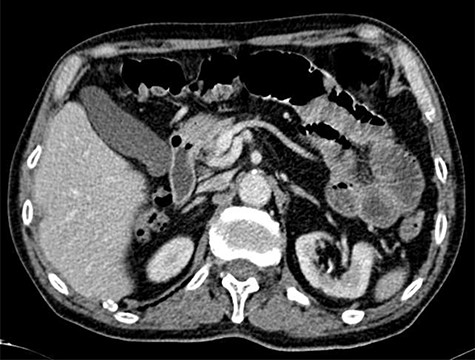

A 82-year-old male presented to our Emergency Department with a history of colicky abdominal pain in the upper quadrants, exacerbated by food and vomiting, suggestive of bowel obstruction. The patient referred intermittent attacks of non-specific abdominal pain over the last weeks. Routine laboratory tests revealed a mild leucocytosis and C-reactive protein elevation, with no further changes. Plain abdominal X-rays revealed multiple dilated loops of small bowel with gas-fluid levels and a subsequent computed tomography (CT) scan confirmed the previous findings, with an area suggestive of small bowel intussusception in the proximal jejunum (Fig. 1).

CT scan targetlike finding. Contrast enhanced CT scan of the abdomen demonstrates the typical multi-layered appearance of a small bowel intussusception. The intussusceptum is accompanied by a mesenteric fat and blood vessels and surrounded by the thick-walled intussuscipiens, the target-like finding, pathognomonic for intussusception.